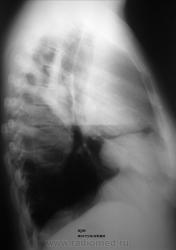

Кстати, про средостение тоже не забывайте-не исключено, что процесс оттуда идет.Справа формируется уровень жидкости, но не совсем понятный.Второй снимок жестковатый, поэтому тень слева не видна четко.

ЛТ в прямой и боковой( обязательно!) проекциях.Если есть возможность сделать УЗИ-не упускайте ее.

С верхнедолевой справа - без вопросов, как и с деструкцией. А вот базально...мне больше импонирует мысль АЛМО по поводу осумкованого плеврита, и знаете, что наводит на эту мысль - полоска просветления между нижним краем затемненной в\доли с затемнением в передне-базальном отделе. если бы это была инфильтрация легочной ткани - этой полоски бы не было, а вот если это коллабированая средняя доля - тогда другое дело и она, эта светлая полоска, вполне обьяснима. Слева - отсев пневмонии в виде овального инфильтрата. Как такое предположение?